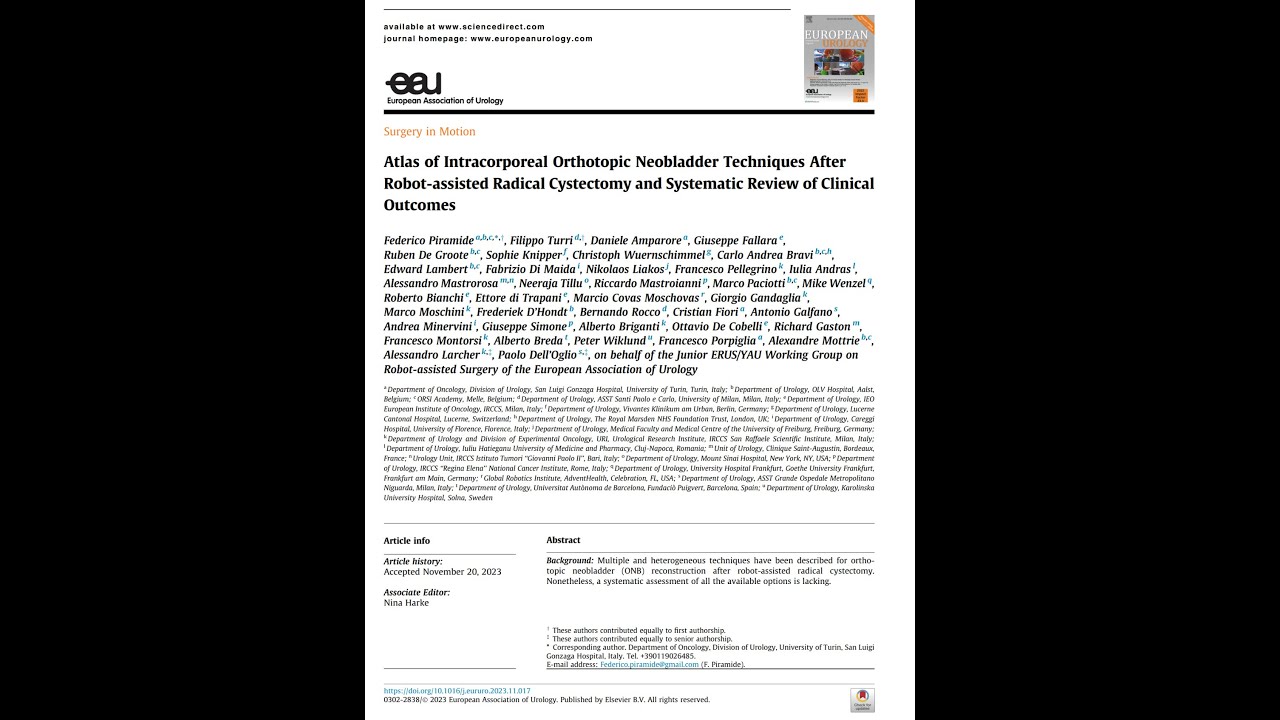

EAU Best Paper Award 2025 Dr. Federico Pirimide

Humans of Robotic Surgery, Robotics, Surgeon, Video Library ';

Best Robotic Surgery Paper in European Urology 2023 Author Interview

Robotics, Surgeon, Urology, Video Library ';